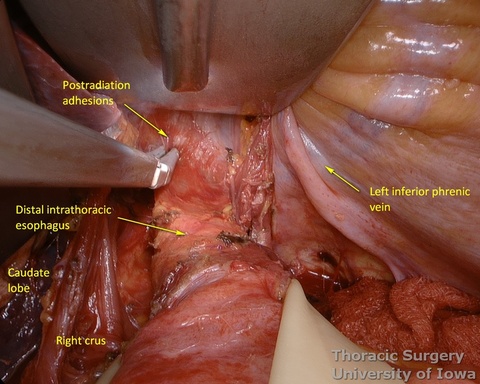

- The mediastinum is entered with the combination of sharp and blunt dissection. Note that postradiation adhesions become denser 4-6 weeks after neoadjuvant treatment.

- Once the mediastinum entered, the manual palpation through the hiatus is performed to assess mobility of the esophagus. Tumor is “rocked” from side to side to make sure it is not adherent to the aorta, prevertebral fascia, or mediastinal structures, thus assuring the feasibility of transhiatal approach or the need to perform transthoracic dissection. This should also be planned based on preoperative imaging.

- The illuminated transhiatal retractor is advanced into posterior mediastinum under direct vision

- The distal thoracic esophagus is visualized.

- Esophagus is circumferentially mobilized under direct vision using combination of sharp and blunt dissection up to the level of the carina.

- Right lateral esophageal “ligament” (attachments to the parietale pleura, pulmonary ligaments and branches of vagal nerves) is exposed are divided under direct vision

- Left lateral esophageal attachments (“ligament") is divided under direct vision

- Aorto-pleural and aorto-esophageal ligaments divide posterior mediastinum into peri-esophageal and peri-aortic (thoracic duct and azygos vein) compartments. They may be distinctly seen in some patients.

- Esophageal arteries (aorto-esophageal branches) and vagal nerves are divided under direct vision using the energy device.

- Periesophageal and subcarinal lymph nodes are dissected separately or en-block with the esophagus under direct vision.

- Use of energy devices should be limited near the membranous portions of the airways.

- Dissection of the distal and mid esophagus is completed using a combination of an energy device and suction tips.

- Through the abdomen, the hiatus is enlarged to allow a hand entry. Circumferential midesophageal and proximal esophageal dissection is gently completed in the superior mediastinum with fingers sequentially through the neck incision (along with gently traction on the cervical esophagus) and hiatus (along with gently traction on the Penrose around the gastroesophageal junction).